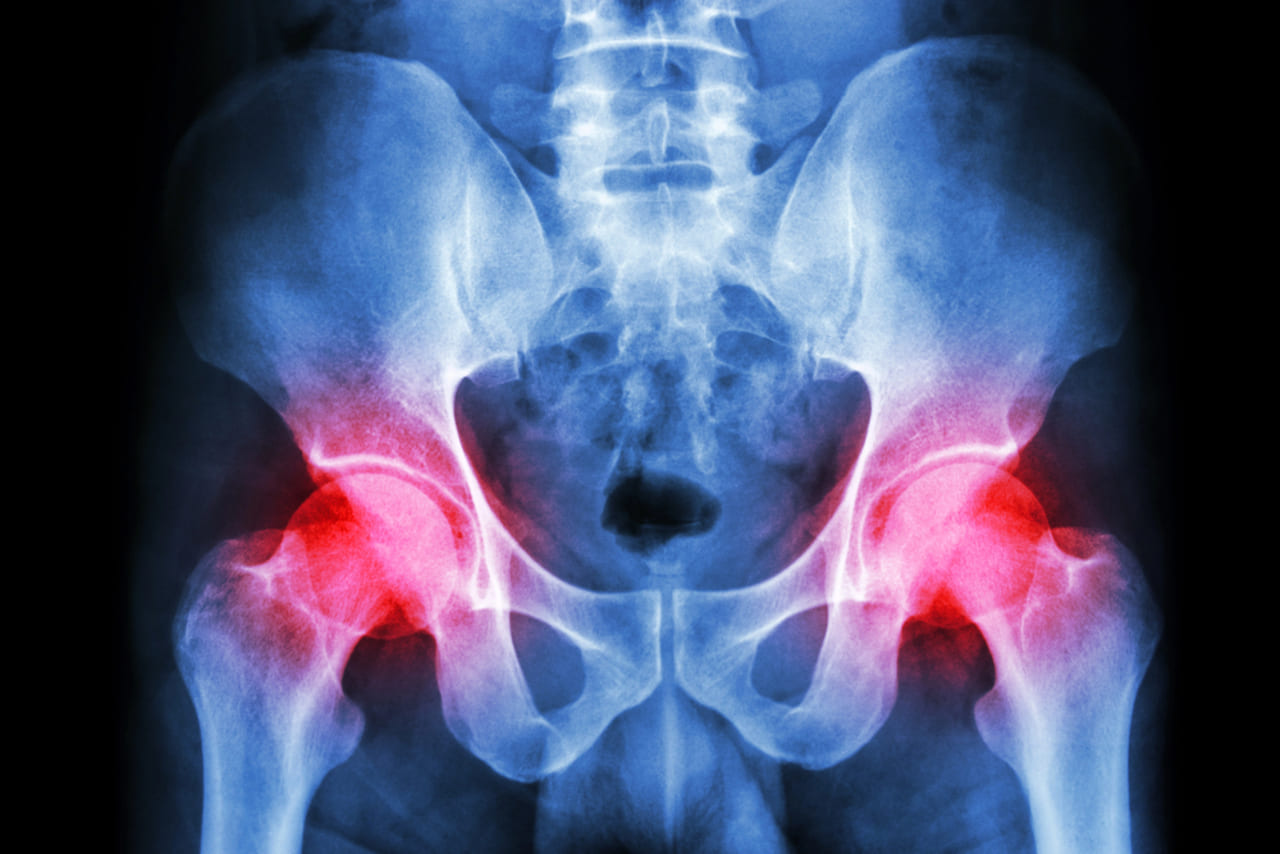

Pelvic floor physiotherapy is a specialized branch of physiotherapy that focuses on the muscles, ligaments, and tissues that support the pelvic organs. This type of therapy is essential for managing various conditions that affect the pelvic region, including incontinence, pelvic pain, and pelvic organ prolapse. In this blog, we will explore when it is appropriate

The pelvic floor plays an essential role in maintaining overall health, supporting vital functions like bladder control, core stability, and organ health. Yet, it’s often overlooked until issues arise. Pelvic floor strengthening is a targeted approach to improving these muscles, providing relief from discomfort, enhancing function, and aiding in recovery from conditions like incontinence or